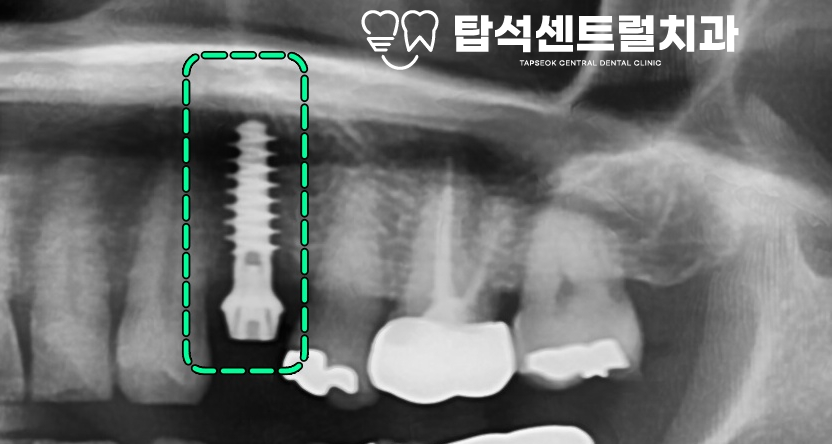

엑스레이 상에서 보았을 때

특수한 나사 구조를 보이고 있어

치조골과 닿는 표면적이 넓고,

나사선 사이 치조골이 거의 훼손되지 않기에

골 흡수가 거의 나타나지 않습니다.

더불어, 안쪽 골막과 분리되지 않아

피질 골이 흡수되지 않는다는

특징을 가지고 있습니다.